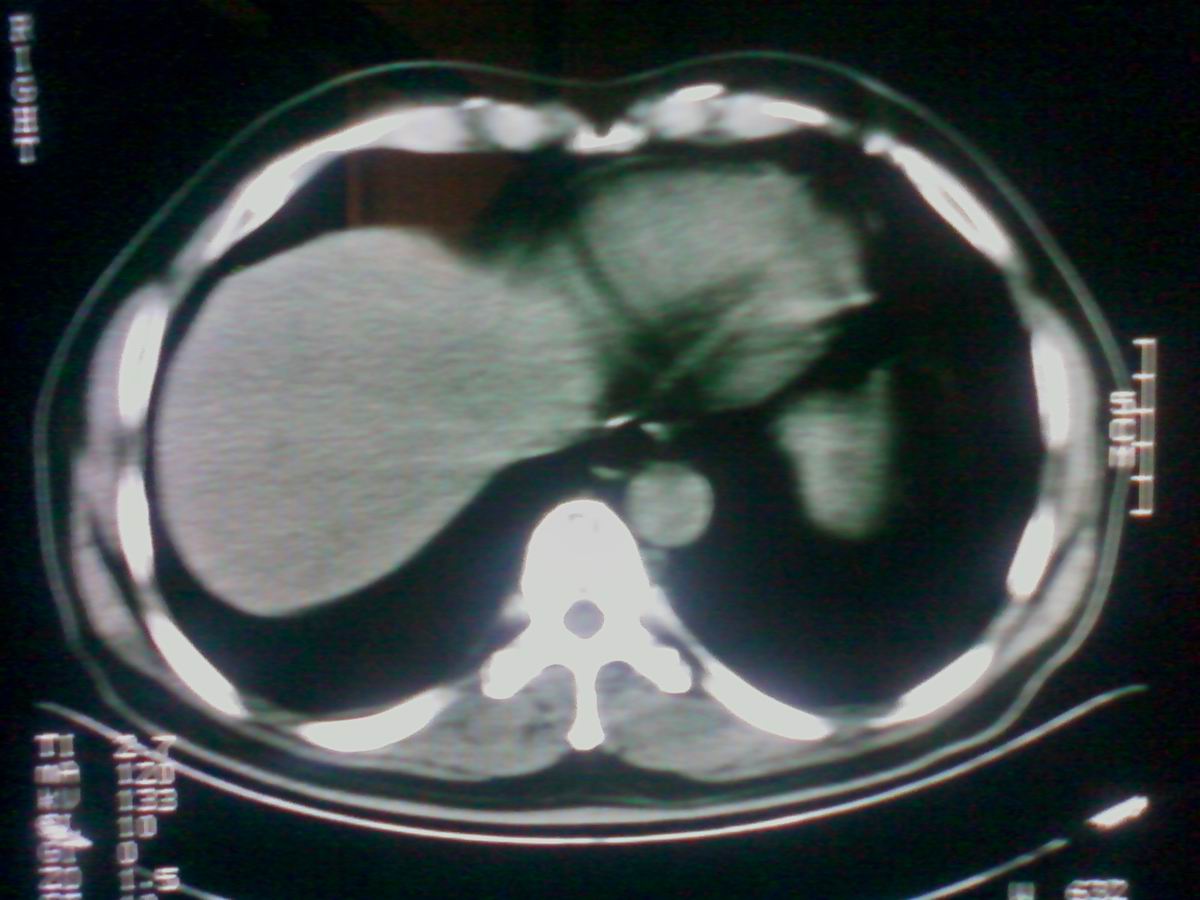

气管后部见半圆形软组织密度病灶,考虑占位,建议气管镜除外鳞癌。

气管上段的肿瘤多为良性乳头状瘤,气管下段的肿瘤多为鳞癌,气管中段的良恶性各占一半。本例位于气管下段,先按恶性处理。不过纤支镜是免不了的。

气管有占位鳞癌、腺样囊性癌、类癌、粘液表皮样癌。